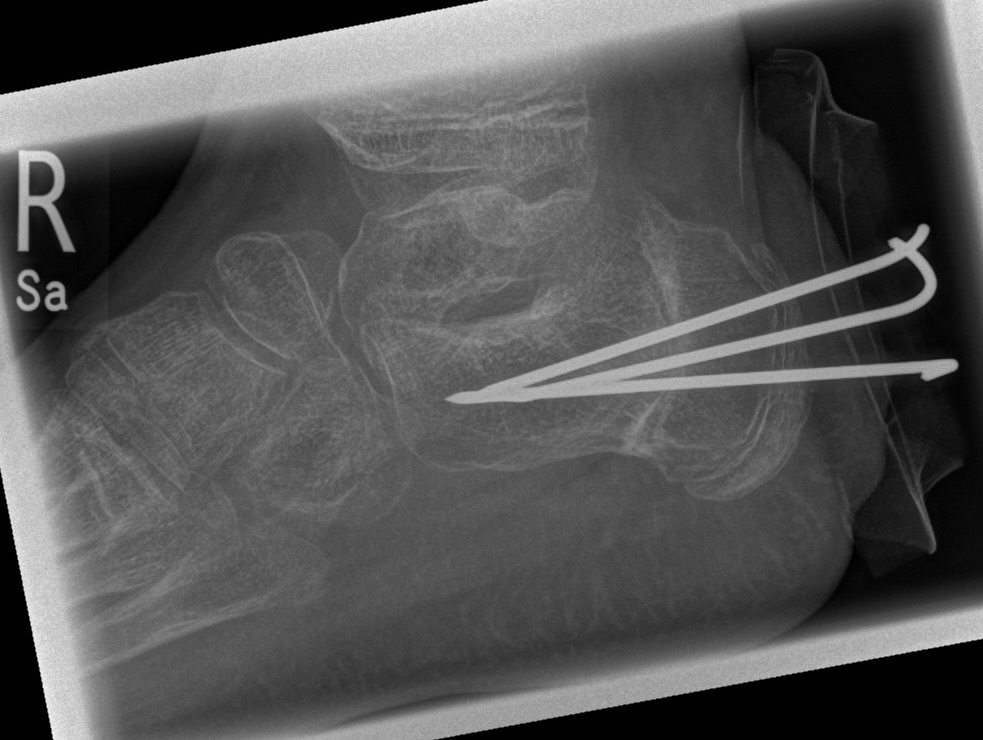

Calcaneus-Osteotomie

Die minimalinvasive Calcaneusverschiebeosteotomie bietet eindeutige Vorteile gegenüber dem offenen Verfahren, sodass wir bei Kindern und Jugendlichen nahezu keine offene Verschiebeosteotomie mehr durchführen. Am Calcaneus liegt die offene Wachstumsfuge dorsal. Bei der Durchführung müssen Schenkel der V-förmigen Osteotomie daher etwas steiler angelegt werden, in einem stumpfen Winkel (siehe Abb. 3 a-j). Für die Osteotomie liegen unsere Patienten auf dem Rücken und der BV wird für die exakte Seitaufnahme eingestellt. Der Fuß lagert auf einem hohen OP-Kissen und die Osteotomie kann bequem mit einem langen Kirschner-Draht und einem sterilen Stift angezeichnet werden (Abb. 15).

Damit lässt sich im Verlauf Röntgenstrahlung für die jungen Patienten vermeiden und die minimalinvasive Osteotomie kann sicher durchgeführt werden. Anschließend erfolgt die Verschiebung oder Impaktion. Ist ein Gleiten nach plantar oder cranial des distalen Fragmentes erwünscht, wird die Osteotomie schräg ohne V-Form entweder verlängernd oder verkürzend durchgeführt (Abb. 16).

Durch den knöchernen Defekt der Fräse gelingt die Verschiebung bei der minimalinvasiven Osteotomie im Fall von strukturell festen Klumpfüßen mit starkem Zug der verkürzten Achillessehne oder bei einer fixierenden spastischen Grunderkrankung einfacher gegenüber dem offen Verfahren. Ein weiteres Plus bei hyperaktiven Weichteilen ist die Vermeidung der ungewollten Cranialisierung des dorsalen Fragmentes durch die V-förmige Osteotomie (Abb. 16).

Die minimalinvasive Calcaneusverschiebeosoteotomie kommt somit in der Versorgung von kindlichen und jugendlichen Fußdeformitäten in einem weiten Erkrankungsspektrum zum Einsatz (Abb. 16):

- Plattfuß – Varisation

- Klumpfuß residual – Valgisation und ggfs. Cranialisation sowie Impaktion

- Klumpfuß überkorrigiert – Varisation und ggfs. Plantarisierung

- Hohlfuß – Cranialisation und ggf. Valgisation (alternativ minimalinvasive Austin-Osteotomie)

Abb. 16 a-f: Varisation einer valgischen Calcaneusstellung bei Knick-Senk-Fuß mit V-förmiger Osteotomie axiale Ansicht (a), seitliche Ansicht (b), d. p. Ansicht (c) und nach Entfernung der Drähte seitliche Ansicht (d), Caudalisierung des dorsalen Calcaneus bei iatrogenem Plattfuß nach Klumpfußüberkorrektur (e) und Cranialisierung beim Hohlfuß (f).

Zum Lesen der Bildbeschreibung und zur Vollansicht bitte die Bilder anklicken. Bilder: A. Helmers.